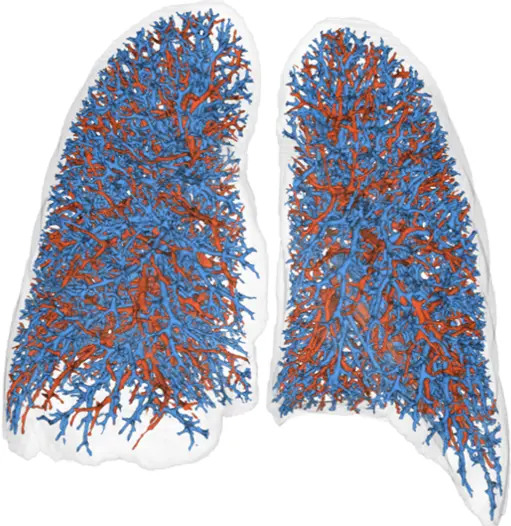

Through our partnership with Thirona, we deliver advanced respiratory image quantification, including bronchial tree analysis and precise, non-invasive vascular analysis, to support more accurate and sensitive phenotyping of pulmonary disease(s) and evaluation of treatment efficacy.

- Airway Analysis, including LungQ® Bronchial-Artery (BA), wall thickening, and mucus plugging assessments*

- Pulmonary Vascular Analysis, including LungQ®-AVX for pulmonary artery-vein phenotyping*